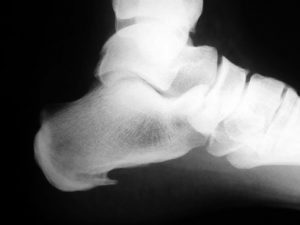

El diagnóstico se realiza a través de la anamnesis y la exploración física. En las pruebas de imagen (radiografía, ecografía…) se puede apreciar a veces, un espolón en el calcáneo (figura 3) o un engrosamiento de la fascia. Pero en pacientes asintomáticos también se pueden apreciar este tipo de hallazgos. Lo más importante es que aunque el diagnóstico por imagen puede ser usado en el manejo clínico de la fascitis plantar, generalmente no cambia el tratamiento del paciente.